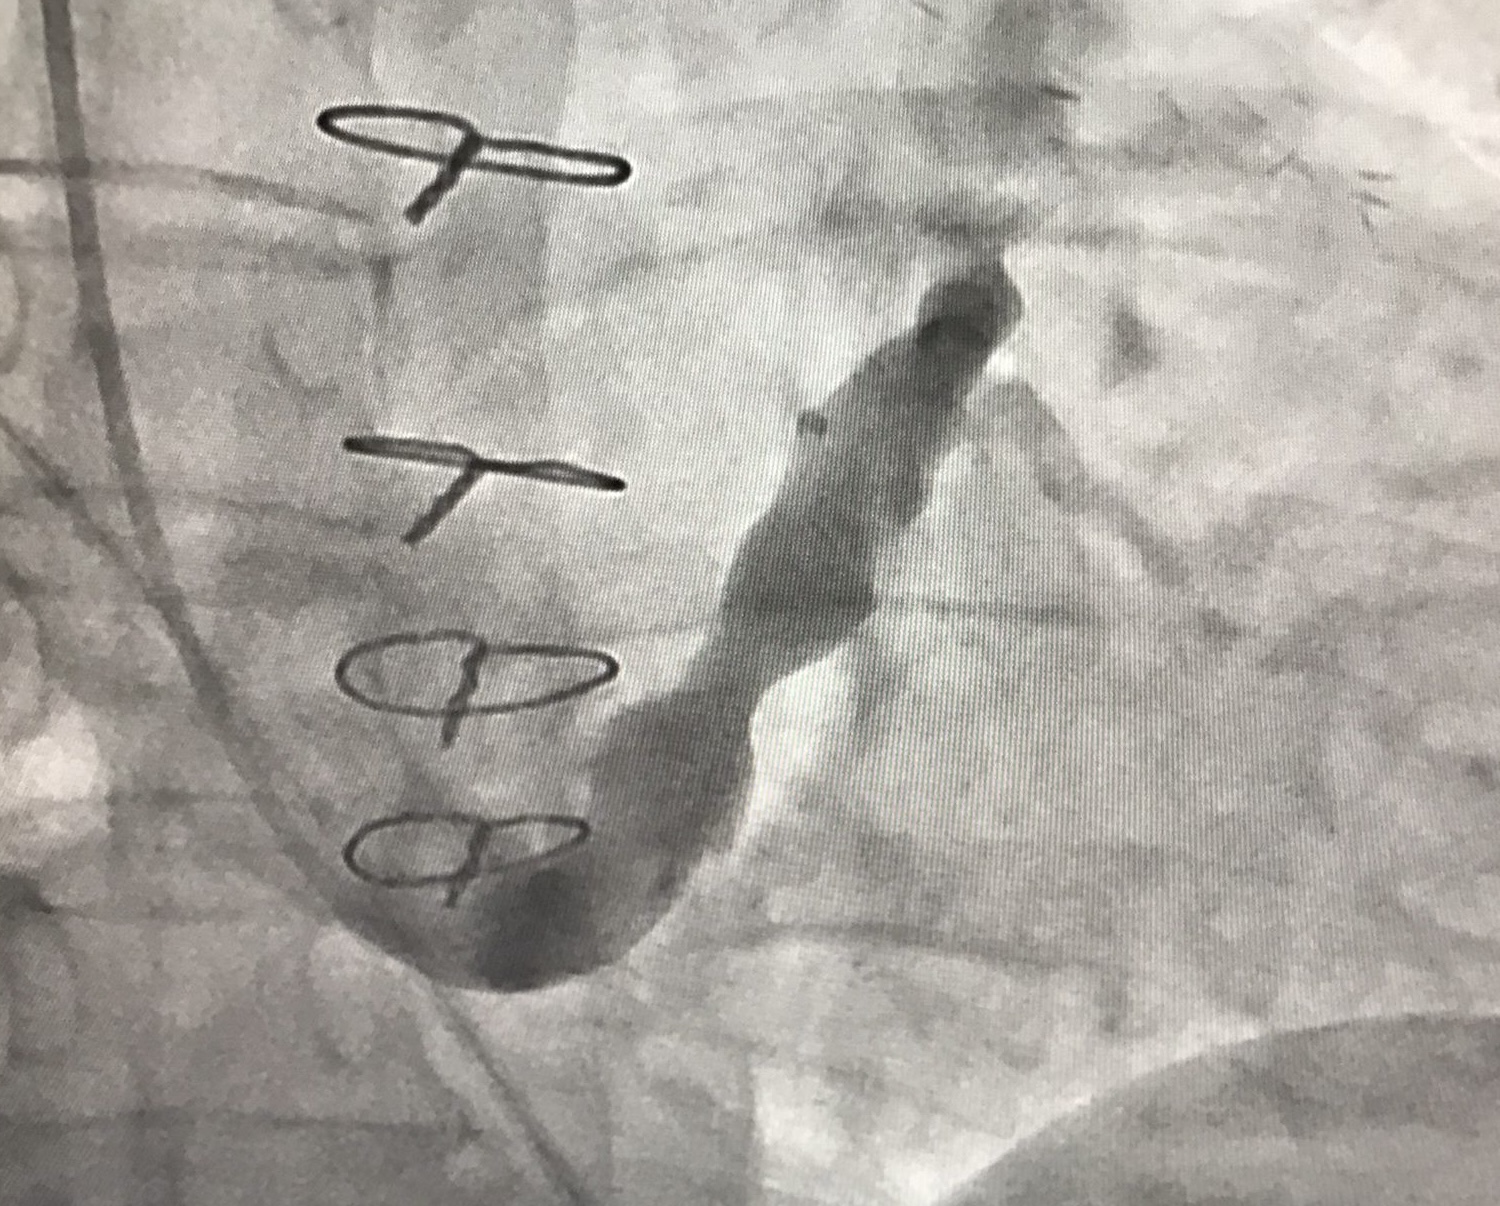

– Zabieg wykonuje się z dostępu przez żyłę szyjną wewnętrzną. Polega on na implantacji dedykowanego stentu w kształcie klepsydry do zatoki wieńcowej, który powoduje kontrolowane jej zwężenie i następnie zwiększenie ciśnienia w układzie żylnym serca. Tym samym dochodzi do redystrybucji krwi w unaczynieniu wieńcowym z miejsc o mniejszym ukrwieniu do miejsc dotychczas niedokrwionych, poprawy perfuzji w mikrokrążeniu serca i redukcji objawów dławicy. Sam zabieg trwa zwykle kilkadziesiąt minut, wykonywany jest w znieczuleniu miejscowym, pod kontrolą fluoroskopii i kontrastu. Pacjent zazwyczaj może być wypisany ze szpitala następnego dnia. Poprawa objawów następuje zazwyczaj w ciągu kilku tygodni od implantacji, a efekty utrzymują się w obserwacji długoterminowej - wyjaśnia prof. Miłosz Jaguszewski.

– Wykorzystany implant to nowatorskie rozwiązanie inżynieryjne przypominające kształtem klepsydrę, które pozwala na bardziej elastyczne dopasowanie się do warunków anatomicznych zatoki wieńcowej. Urządzenie to znajduje się obecnie w fazie oceny rejestracyjnej przez amerykańską Agencję Żywności i Leków (FDA). Nasz udział w jego wdrożeniu potwierdza wysoką pozycję UCK w Gdańsku na arenie międzynarodowej jako ośrodka referencyjnego w zakresie nowoczesnej terapii dławicy opornej – zaznacza dr Dariusz Ciećwierz, koordynator Pracowni Kardiologii Inwazyjnej UCK.